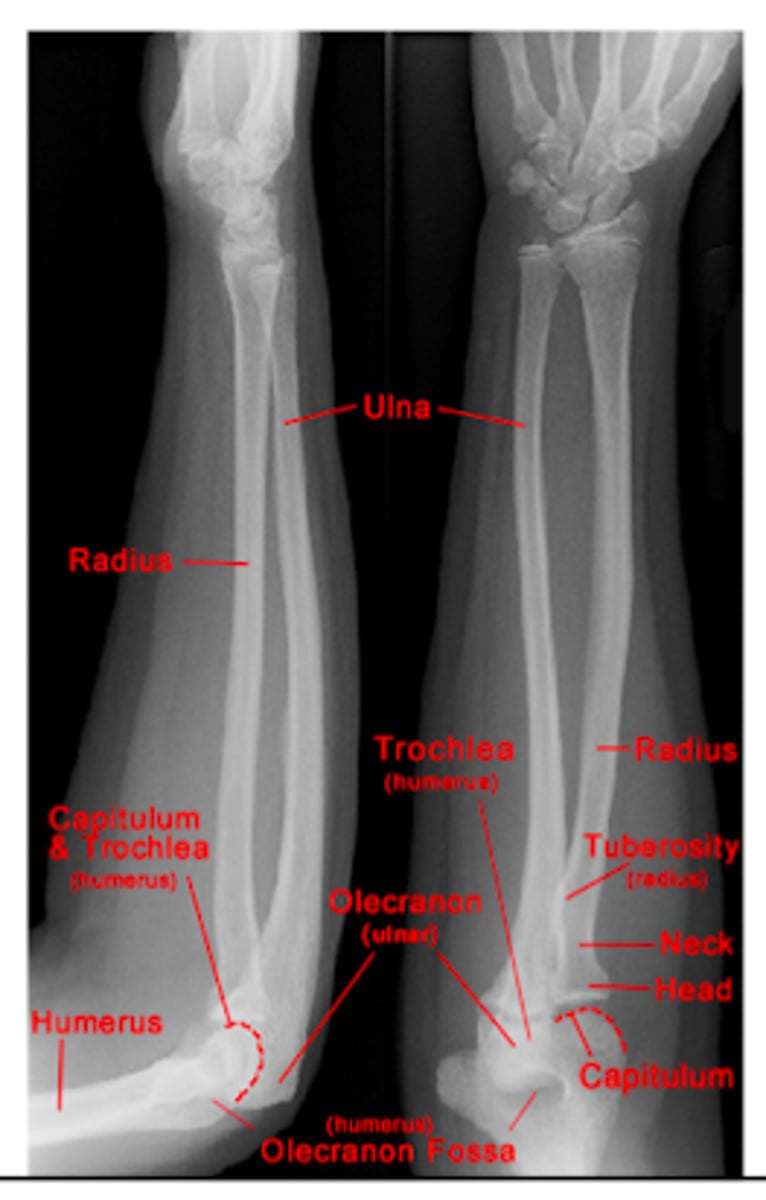

REVIEW: XR of elbow (AP view)

REVIEW: XR of the forearm.